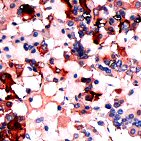

Immunohistochemistry (Formalin/PFA-fixed paraffin-embedded sections) - Anti-TSH antibody (AB64378)

ab64378, at a dilution of 1/200, staining TSH in formalin fixed, paraffin embedded human anterior pituitary tissue by Immunohistochemistry.